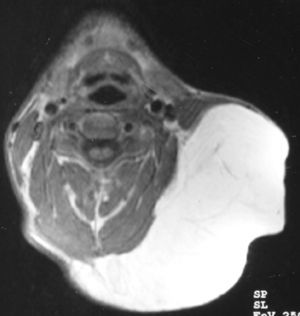

Se decide realizar resonancia magnética (RM) cérvico-facial en la que se evidencia una masa homogénea, bien delimitada que no invadía estructuras vecinas y con una densidad grasa (figs. 2-4).

Las técnicas de imagen como la RM nos ayudan a determinar la exacta localización y las relaciones de la masa con las estructuras anatómicas de la vecindad. Estos tumores aparecen como masas homogéneas y radiolúcidas tanto en la RM como en las radiografías. En las RM son isointensas en relación con la grasa subcutánea8,9.